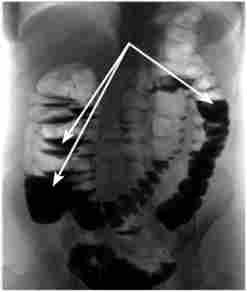

Для уточнення діагнозу застосовуються інструментальні методи дослідження. Всім хворим з підозрою на гостру кишкову непрохідність виконується оглядова рентгенограма живота. Знімок робиться у вертикальному положенні хворого в прямій проекції. Якщо через важкість стану хворий не може стояти на ногах, дослідження виконують в латеропозіції (горизонтальне положення на боці). У сидячому положенні досліджувати хворого не варто, так як при цьому на знімку видно лише верхня половина живота. Наявність на рентгенограмі горизонтальних рівнів рідини зі скупченням внутрикишечного газу над ними (чаш Клойбера) - основний рентгенологічний ознака ОКС (рис. 23.4).

Оглядова рентгенограма живота

Мал. 23.4. Оглядова рентгенограма живота.

Чаші Клойбера (вказані стрілками)